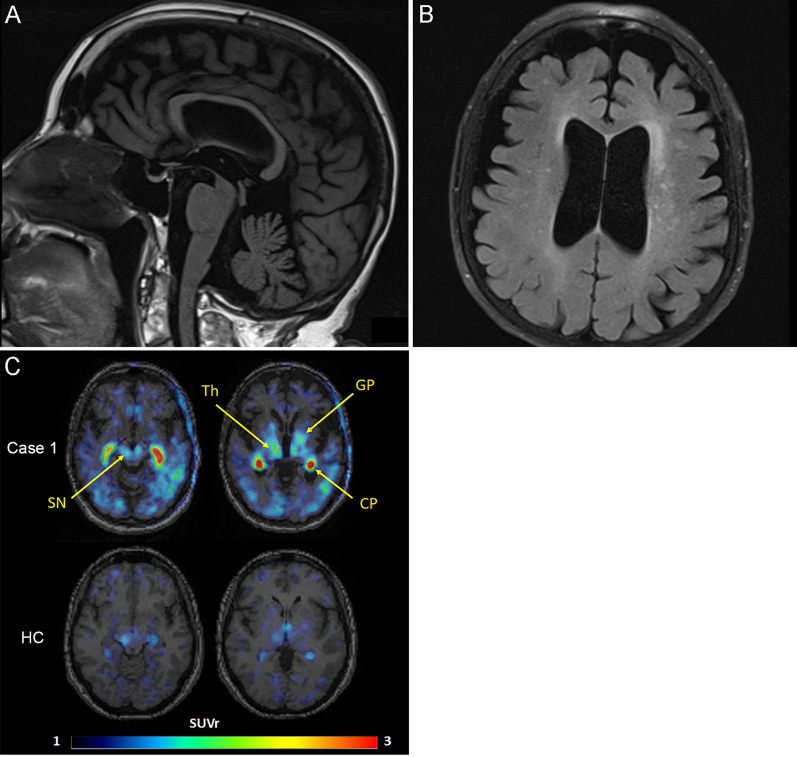

The patient was a 75-year-old woman whose mother and sister had diagnoses of PSP. She presented with frequent falls at age 70, followed by bradykinesia. She developed urinary incontinence at age 72 and began having dysarthria, dysphagia, and diplopia at age 74. The neurological examination at age 74 revealed vertical gaze palsy in both directions, square wave jerks, mild spastic dysarthria, rigidity in the neck and extremities, bradykinesia, postural instability, and an unstable gait that required assistance. She also had a dystonic posture of left upper extremity and asymmetric motor difficulty worse on the left. Deep tendon reflexes were symmetric and within normal limits, but a Babinski sign was present on the left. No tremor, myoclonus, apraxia or orthostatic hypotension were observed. The total PSP Rating Scale score was 53 (Table 1) [ref. 12], typical for her symptom duration of 5 years. She scored 17/30 on the Montreal Cognitive Assessment, consistent with moderate cognitive impairment. Her deficits were characterized by impairments in visuospatial function, naming, attention, and delayed recall. The applause sign and antisaccade task were weakly abnormal. MRI of the brain revealed atrophy of the midbrain and mild, slightly asymmetric cerebral atrophy (Fig. 1A, B). An [18F]APN-1607 positron emission tomography (PET) scan revealed low-to-moderate uptake in a defined subset of brain structures, such as substantia nigra, globus pallidus, thalamus and posterior cortical areas, including temporal, parietal and occipital cortices (Fig. 1C). Low intensity signal was also noted across cortical regions, especially in the temporal lobes and posteriorly. Strong non-specific signal was also noted in choroid plexus, which is inconsistently seen with this tracer [ref. 38], but is not diagnostically significant. She was clinically diagnosed with probable PSP-Richardson syndrome.

Case 1 underwent dynamic PET imaging following intravenous administration of 5.66 mCi [18F]APN-1607 on a Siemens HR + PET camera. Images were obtained from 0–90 and 120–180 min post-injection. Images were reconstructed in a 128 × 128 matrix (zoom = 2) with an iterative reconstruction algorithm (ordered subset expectation maximization), with random, attenuation and scatter corrections. Images were co-registered with 1 mm contiguous T1 MP-RAGE MRI images to delineate the anatomical regions of interest. Images are presented here as standardized uptake values from 60–90 min relative to a ventral cerebellar reference region (SUVr).